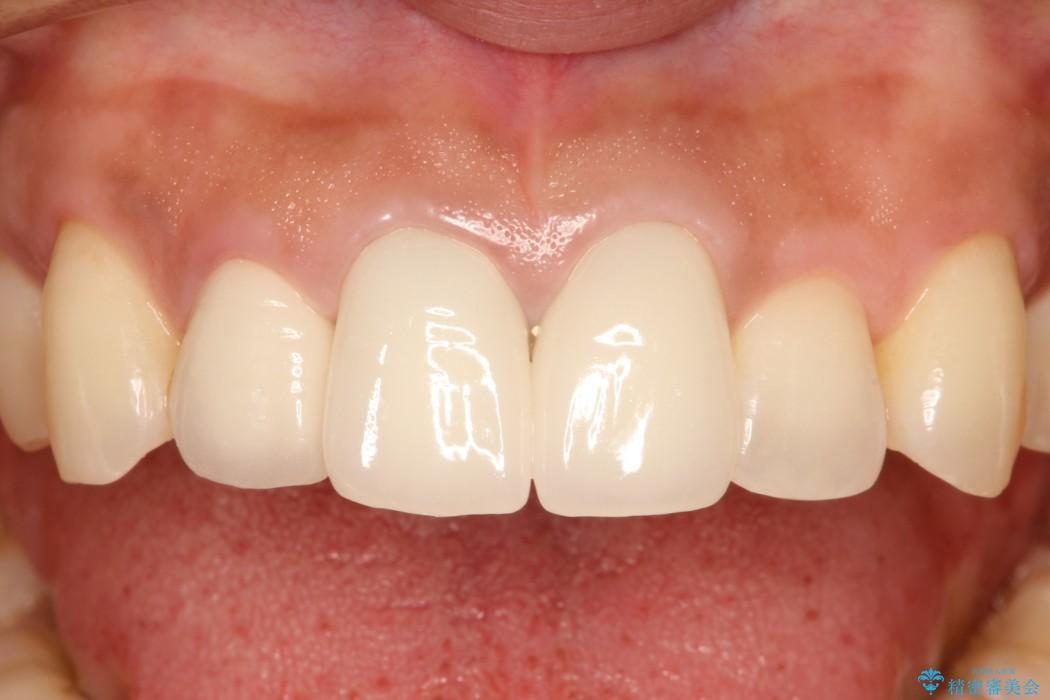

被せものを外し、金属の土台を白い土台にやり替えてから、金属を用いないオールセラミッククラウンによる治療をご提案しました。

金属を用いた治療では、時間が経過していくと口腔内に金属イオンが徐々に溶出し、歯や歯肉が黒くなることがあります。

審美的なことも考慮して、前歯には金属を使用しないオールセラミッククラウンがおすすめです。